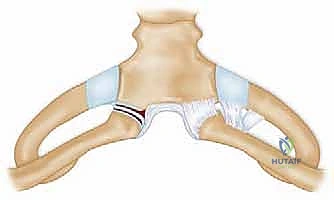

لا يمكن ببساطة خياطة الأربطة الممزقة لضمان الاستقرار. لذلك، يستخدم الدكتور هطيف تقنية متقدمة لإعادة البناء باستخدام "رقعة وترية" (Tendon Graft).

* حفر الأنفاق العظمية: يتم حفر ثقوب دقيقة جداً في عظم الترقوة وعظم القص باستخدام أدوات جراحية متطورة.

5. تمرير الرقعة وتثبيتها (تقنية الرقم 8)

يتم تمرير الرقعة الوترية عبر الثقوب العظمية بنمط يشبه الرقم 8 (Figure-of-eight). هذه التقنية الميكانيكية الحيوية توفر قوة استقرار هائلة تحاكي قوة الأربطة الطبيعية (الرباط الكبسولي والرباط الضلعي الترقوي).

تحذير طبي هام: في الماضي، كان بعض الجراحين يستخدمون أسياخ معدنية (K-wires) لتثبيت المفصل. الأستاذ الدكتور محمد هطيف يمنع تماماً استخدام هذه الأسياخ في هذا المفصل، حيث أثبتت الدراسات الطبية أن هذه الأسياخ قد تهاجر وتخترق القلب أو الرئتين مسببة الوفاة. بدلاً من ذلك، يعتمد الدكتور هطيف على خيوط جراحية فائقة القوة (Suture anchors) والرقع الوترية الطبيعية التي تندمج مع الجسم.